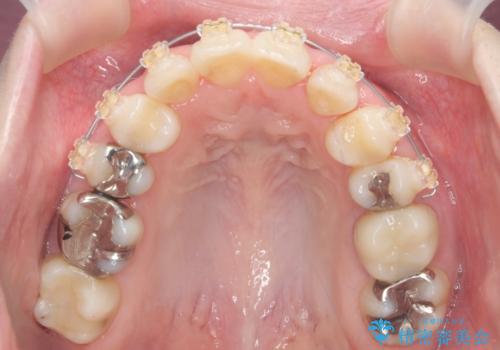

八重歯の部分は抜歯し、奥に入っていた前歯を前に移動させました。

下の前歯は生まれつき3本だったため、さらに2本下を抜くとなると3本少なくなってしまうため、下の前歯を一本お取りして最小限の抜歯としました。

上にはワイヤー部分矯正を行った後、インビザラインでマウスピース矯正を行っています。

今回は特に左上の犬歯は歯肉退縮して根が露出していたのもあり、抜歯をお勧めしました。